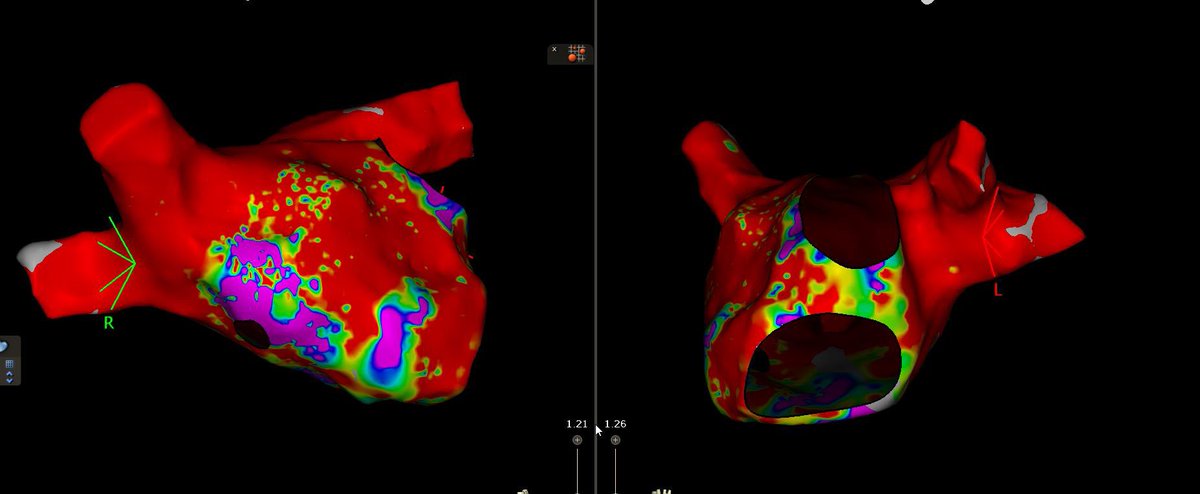

A case of the missing 20ms… Despite double ant line, mitral flutter didn’t terminate. Map shows incomplete histogram due to epi bridge. Found endo landing zone laterally on base of appendage #EPeeps AFPanico Alex Turin Gina Glover Roderick Tung Amin Al-Ahmad, MD Anand